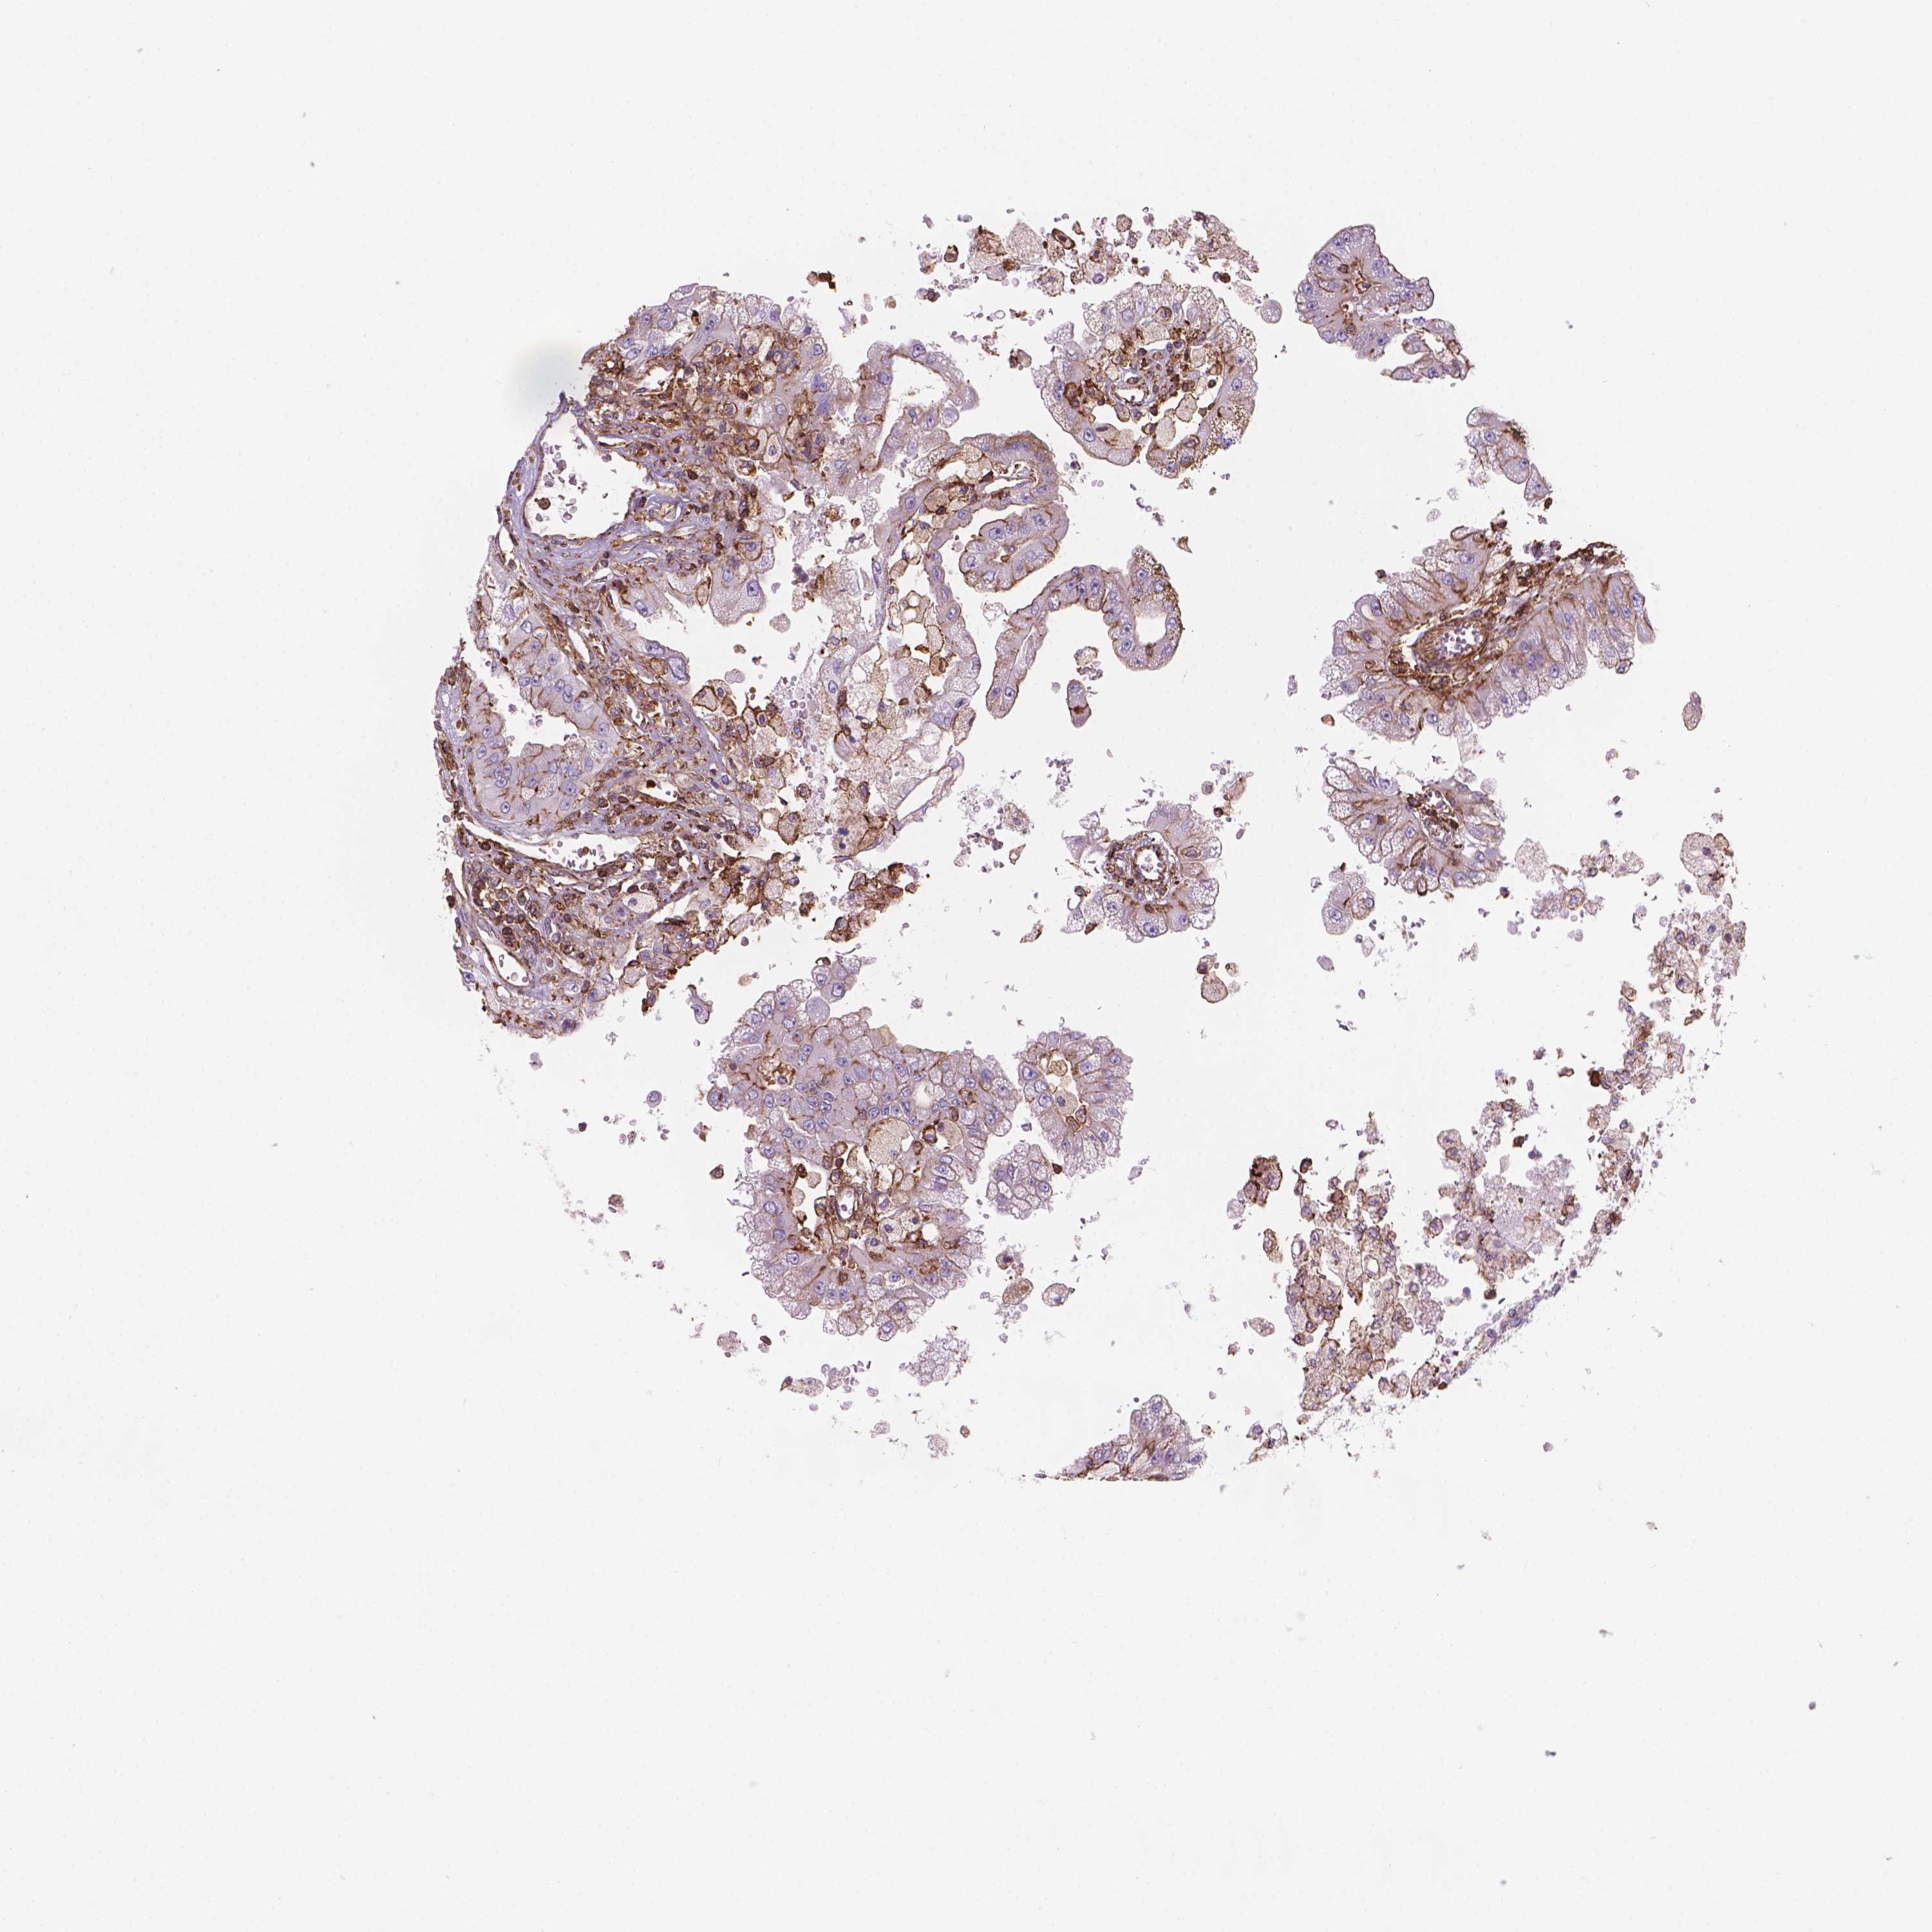

KIDNEY RENAL CLEAR CELL CARCINOMA (TCGA) - Interactive survival scatter ploti

The Survival Scatter plot shows the clinical status (i.e. dead or alive) for all individuals in the patient cohort, based on the same data that underlies the corresponding Kaplan-Meier plots. Patients that are alive at last time for follow-up are shown in blue and patients who have died during the study are shown in red.

The x-axis shows the expression levels (FPKM) of the investigated gene in the tumor tissue at the time of diagnosis. The y-axis shows the follow-up time after diagnosis (years). Both axes are complimented with kernel density curves demonstrating the data density over the axes. The top density plot shows the expression levels (FPKM) distribution among dead (red) and alive patients (blue). The right density plot shows the data density of the survived years of dead patients with high and low expression levels respectively, stratified using the cutoff indicated by the vertical dashed line through the Survival Scatter plot. This cutoff is automatically defined based on the FPKM cutoff that minimizes the p-score. The cutoff can be changed by dragging the vertical line or by entering a cutoff value in the square labeled "Current cut-off".

Under the Survival Scatter plot the p-score landscape (black curve; left axis) is shown together with dead median separation (red curve; right axis). Dead median separation is the difference in median mRNA expression between patients who have died with high and low expression, respectively. It is calculated as follows: median FPKM expression of dead patients with high expression - median FPKM expression of dead patients with low expression. This is intended to aid the user in visually exploring custom cutoffs and the associated p-scores and dead median separation.

Individual patient data is displayed and can be filtered by clicking on one or more of the category buttons on the top of the page. Categories describing expression level and patient information include: high, low, alive, dead, female, male and tumor stages. The scale of the x-axis can be toggled between linear and log-scale by clicking on the "x log" button. Mouse-over function shows TCGA ID, patient information and mRNA expression (FPKM) for each patient.

& Survival analysisi

Kaplan-Meier plots summarize results from analysis of correlation between mRNA expression level and patient survival. Patients were divided based on level of expression into one of the two groups "low" (under cut off) or "high" (over cut off). X-axis shows time for survival (years) and y-axis shows the probability of survival, where 1.0 corresponds to 100 percent.

PATJ is validated prognostic, high expression is favorable in Kidney Renal Clear Cell Carcinoma (TCGA)

Best expression cut offi

Based on the FPKM value of each gene, patients were classified into two groups and association between prognosis (survival) and gene expression (FPKM) was examined. The best expression cut-off refers the FPKM value that yields maximal difference with regard to survival between the two groups at the lowest log-rank P-value. Best expression cut-off was selected based on survival analysis .

When clicking on this number, the vertical dashed line indicating cut-off, the interactive survival plot, and the Kaplan-Meier curve will be adjusted to show results based on the best expression cut-off.

: 16.57

TCGA RNA samplesi

RNA-seq data is reported as average FPKM (number Fragments Per Kilobase of exon per Million reads), generated by the The Cancer Genome Atlas (TCGA) .

Normal distribution across the dataset is visualized with box plots, shown as median and 25th and 75th percentiles. Points are displayed as outliers if they are above or below 1.5 times the interquartile range. FPKM values of the individual samples are presented next to the box plot.

Average pTPM 21.6

Number of samples 521